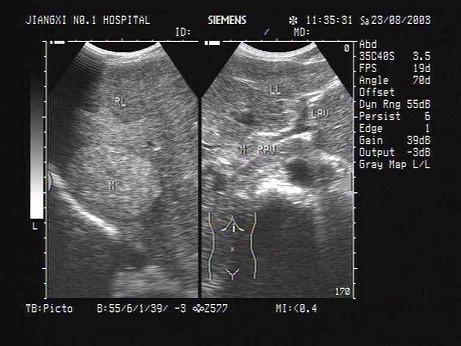

问题 某患者肝脏声像图表现,最可能的诊断是?(?)

选项 A.肝转移癌 B.原发性肝癌并门脉癌栓 C.弥漫性肝癌 D.肝硬化并门脉海棉样变性 E.肝硬化并门脉血栓形成

答案 B